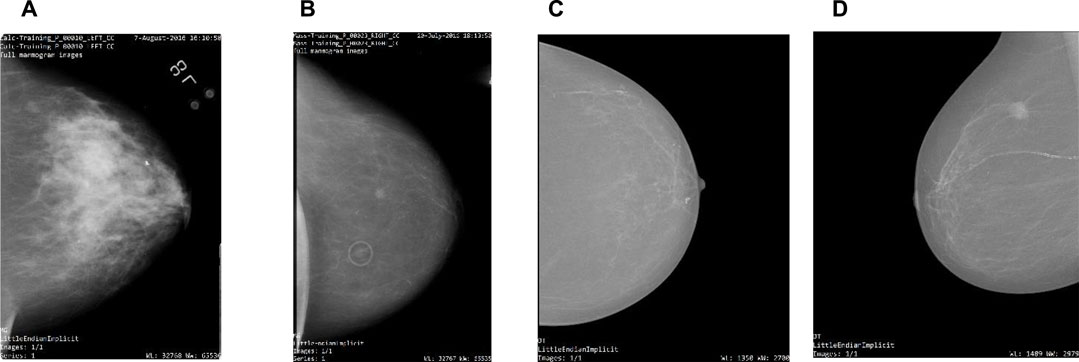

00153-X/asset/006e6fd0-f9ca-4929-a281-d4c073f2d667/main.assets/gr3_lrg.jpg)